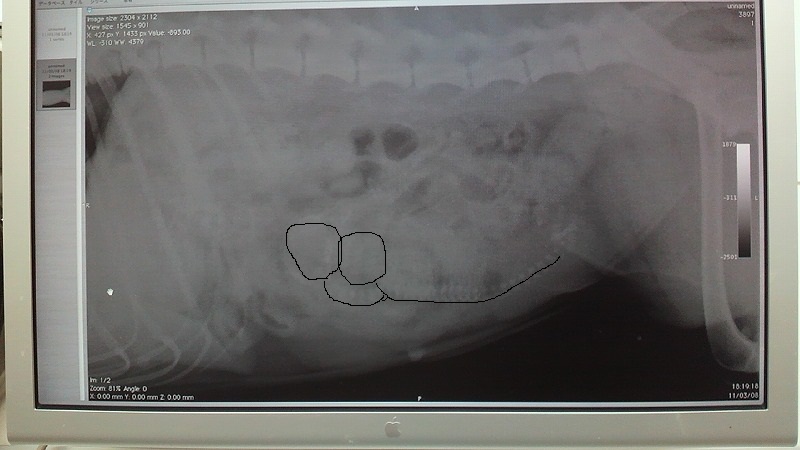

耳の温度一定せんなー